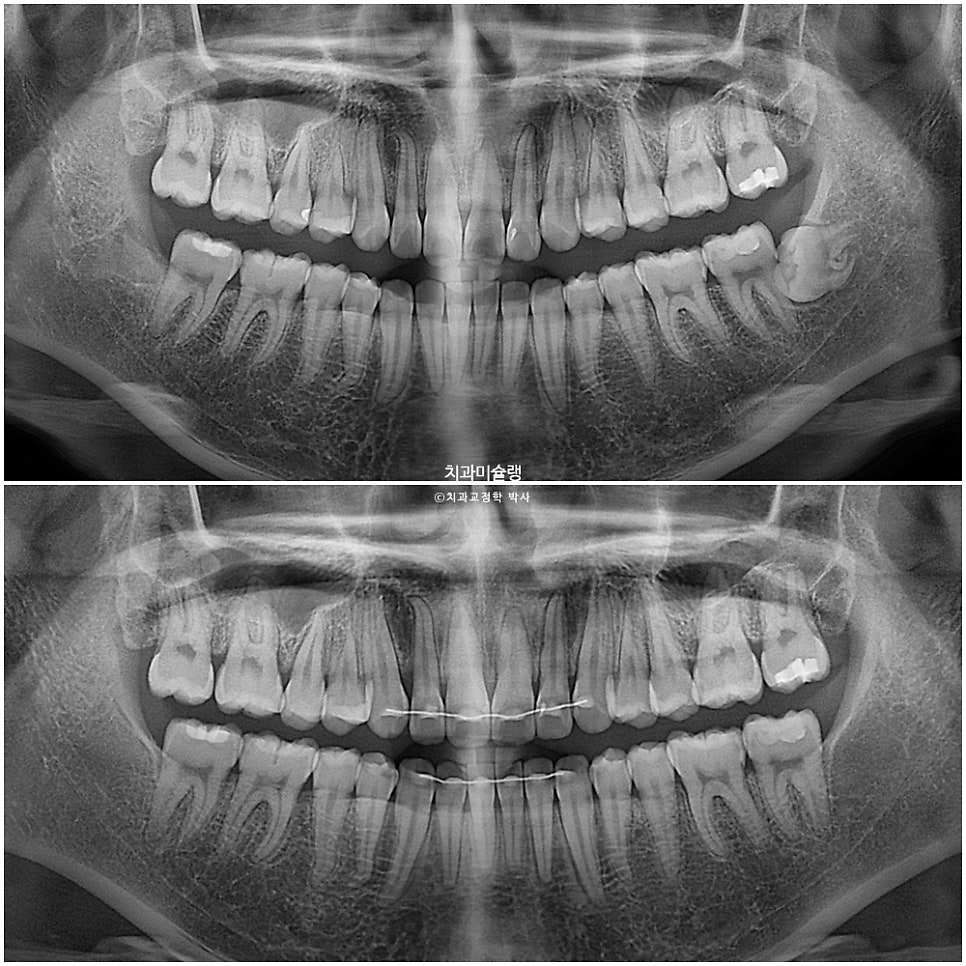

방사선 검사 결과

1년 2개월간 치근흡수는 없으며, 치근평행도는 좋습니다. 사랑니 공간으로 어금니들이 잘 이동하였습니다.

교정 전후 옆 엑스레이 중첩입니다. 앞니 돌출이 해소되며 입술이 한결 편하게 다물립니다. 뒤로 밀렸던 턱이 과개교합이 해소되면서 소량 앞으로 나왔습니다.